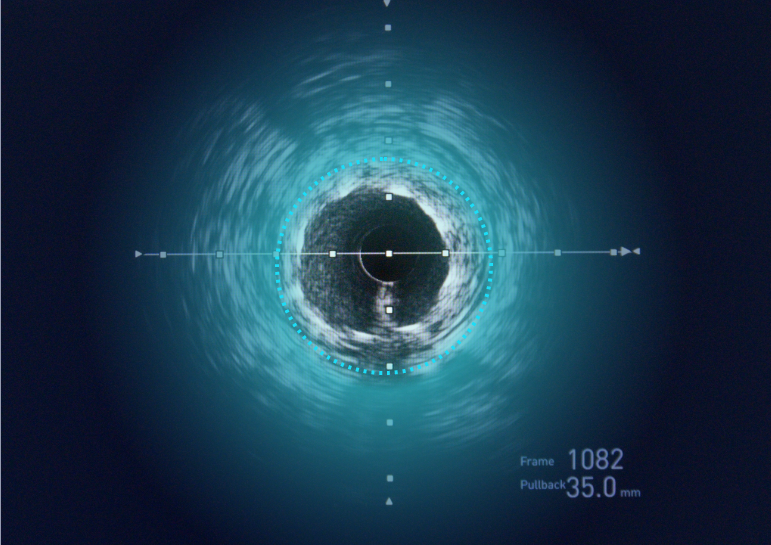

Automated Cardiac Image Analysis and Interpretation

Dyad Medical Inc. |